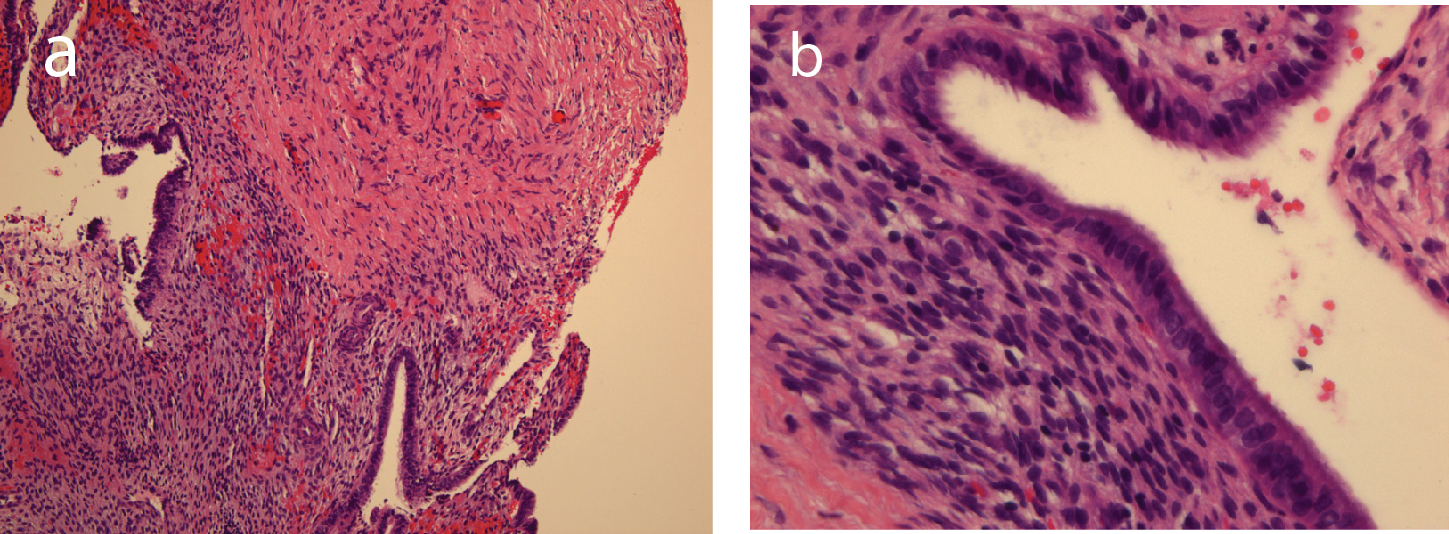

Sections showed bland-appearing endometrial glands with associated endometrial stroma with mild early secretory change and adjacent dense fibrous stroma (Fig. 3A and 3B). Focally, there are clusters of hemosiderin-laden macrophages, consistent with remote hemorrhage, however, no apparent cytological atypia is identified.

Click for large image | Figure 3. Bland-appearing endometrial glands with associated endometrial stroma and adjacent dense fibrous tissue in medium-power photomicrograph (original magnification, ×10; hematoxylin-eosin stain, a), and in high-power photomicrograph (original magnification, ×40; hematoxylin-eosin stain, b). |